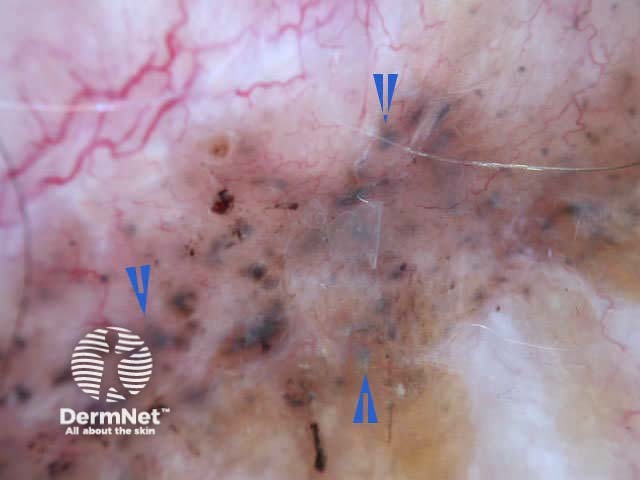

Blue-white structures can refer to any type of blue and/or white colour, i.e. combination of blue-white veil and regression structures, as shown in the following pictures. The colour can be subtle. Not all lesions with blue-white structures are malignant.

Melanoma Basal cell carcinoma Melanoma Lentigo maligna Congenital naevus Blue naevus Dysplastic naevus Dysplastic naevus